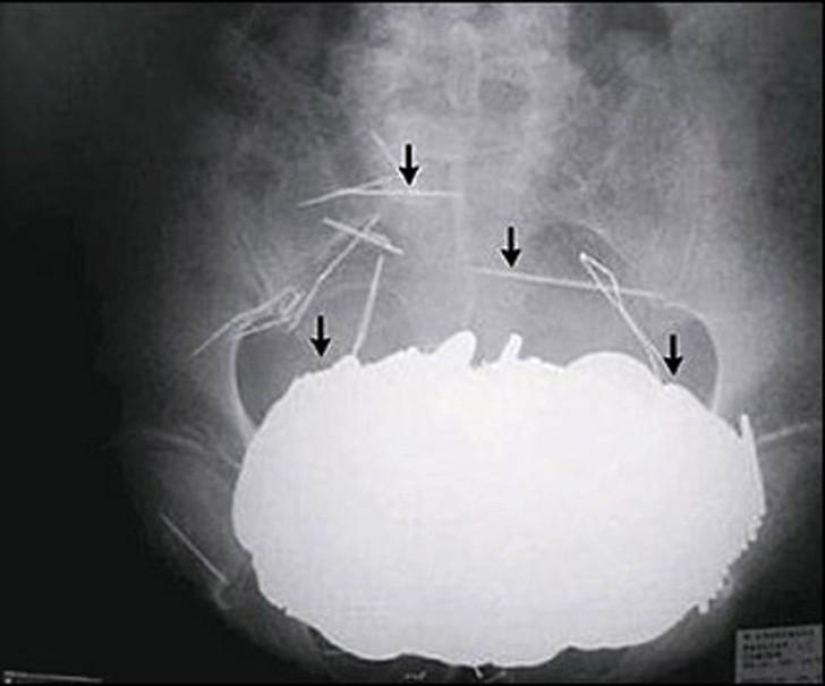

Muelles de cama.